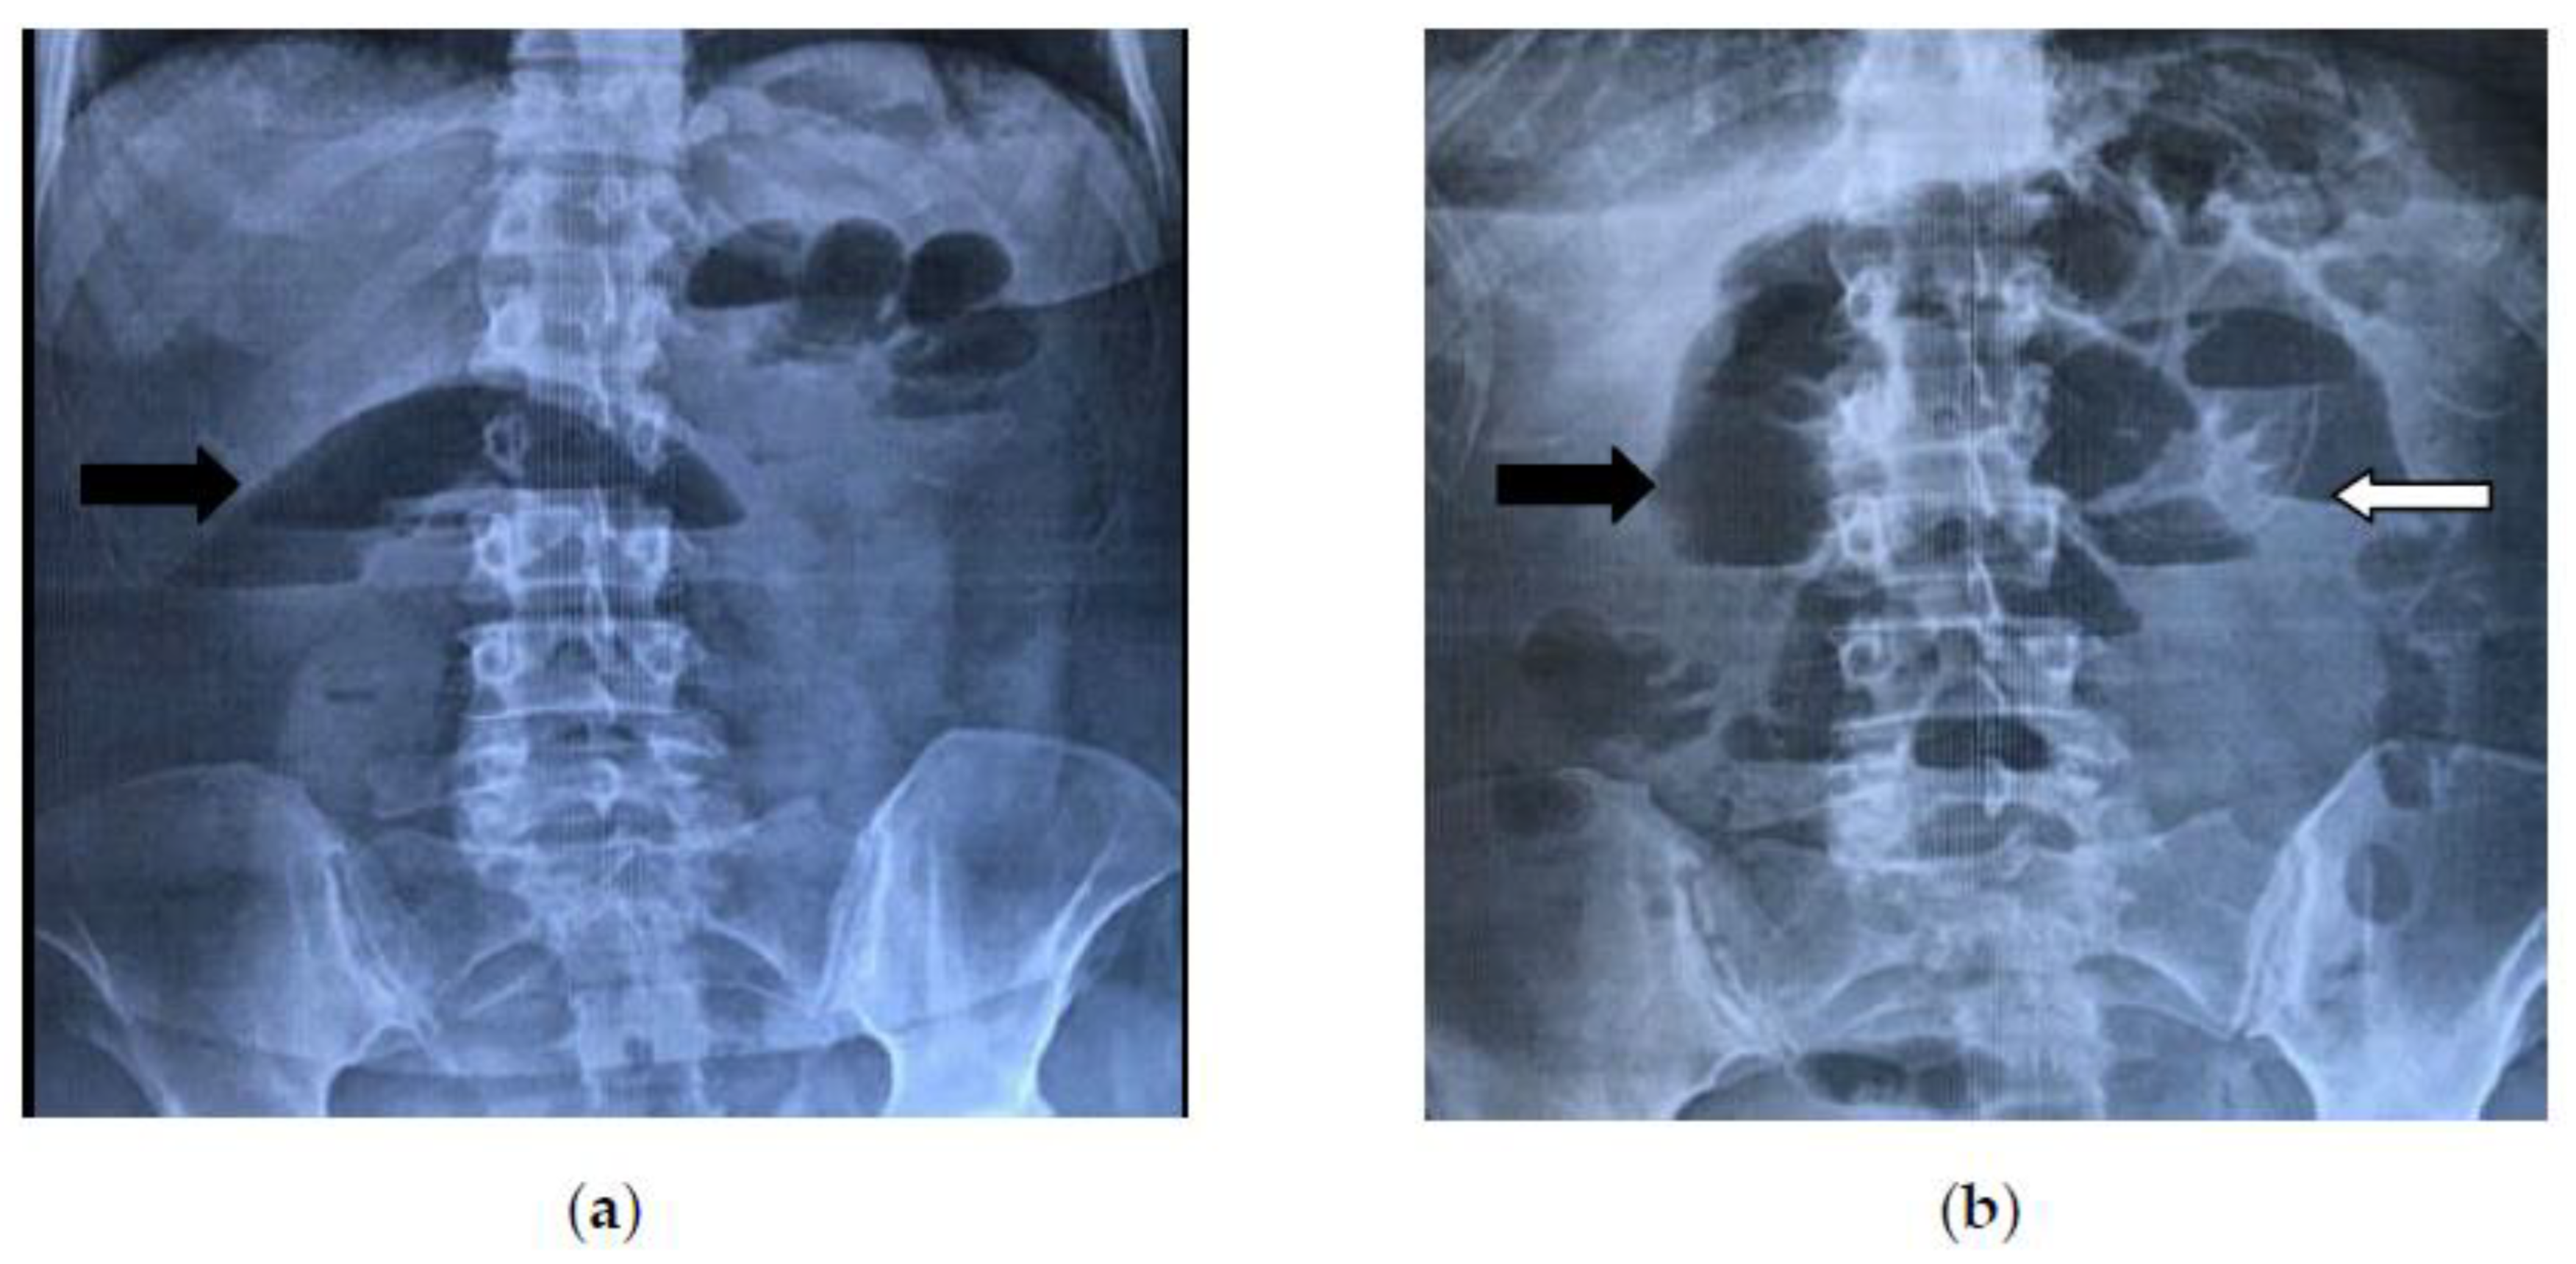

The first case concerned a 48-year-old female patient, who presented to the emergency department with diffuse abdominal pain over the last 24 hours and vomiting. Her medical and surgical history were free. The laboratory results showed an elevated White Blood Cell (WBC) count (17.4 mm3/μL, normal range 4.3-10.3 mm3/μL) and a normal C-Reactive Protein (CRP) value (0,4 mg/dL, normal range < 0,5 mg/dL). Plain abdominal imaging in an upright position revealed air fluid-levels typical for an intestinal obstruction (Figure 1a), whereas the ultrasound examination was non-conclusive. The computed tomography (CT) scan showed a distention of the small intestine until the terminal ileum, without identifying the cause of obstruction. Initially, a nasogastric tube was placed for conservative management. After 48 hours the patient’s condition as well as the plain abdominal imaging (Figure 1b) showed no signs of improvement, so an exploratory laparotomy was decided.

This was later confirmed through a CT scan which revealed an abdominal "mass" with intestinal loops forming a multilayer concentric ring, expanding from the ileocolic valve till the left upper abdomen, suggesting an ileocolic intussusception (Figure 3).

Plain abdominal radiograph in an upright position may reveal signs of intestinal obstruction (distended bowel loops, absence of air in the large bowel) or perforation (free air under the diaphragm). It is a cost effective and sensitive modality in terms of diagnosing bowel obstruction, but it lacks on specificity in determining the exact location and the cause of it (i.e., intussusception) [16]. On the other hand, contrast studies such as barium enema may be helpful in diagnosing patients with colonic intussusception (as in the third case of the present study), but their use is limited in adult patients, especially in an emergency setting [15].

Figure 1. plain abdominal radiograph of the patient (first case) in an upright position, on admission (a) and 48 hours later (b). Air -fluid levels (black arrows) typical for small bowel obstruction are clearly seen in both films, with no signs of improvement after conservative treatment with nasogastric tube (white arrow).

Figure 3. Abdominal CT of the patient (second case) showing an abdominal "mass" (black arrow), consisting from intestinal loops forming a multilayer concentric ring, expanding from the ileocolic valve till the left upper abdomen and suggesting an ileocolic intussusception.